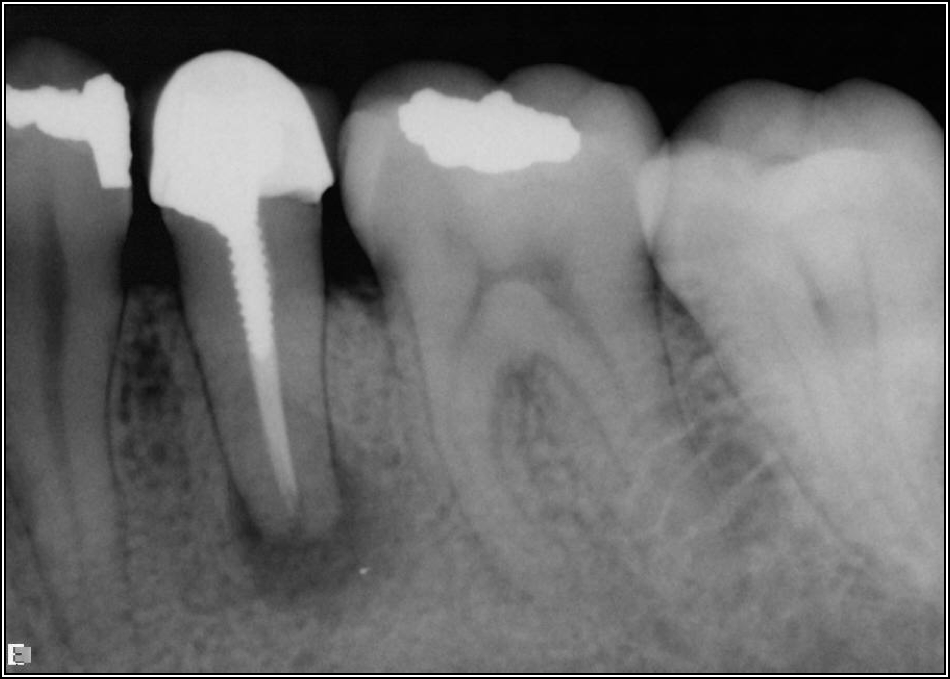

Fig 8. Bitewing revealed decay and other problems.

Figure 8

With the bitewing shown in Figure 8, it became clear there was gross decay in tooth No. 3 that could not be seen on the PA, and there was a periodontal defect, a pulp stone, in No. 2. There was also a class V lesion revealing the bruxism, flat occlusion, multiple restorations in No. 30, a post in No. 31, and decay on No. 2 as well. The post in No. 31 was useless because when a post is placed, it must be the right length, width, and size. If the post is too short, there will be a greater fulcrum and the tooth will break. If it is too long, the clinician can break it by wedging it. If it is too short, it will not hurt the tooth, but it will not provide any valuable function. It is overall preferable to do posts in teeth having just single restorations rather than abutments for bridges because those teeth are already under greater force. If the technique is not performed correctly, iatrogenic issues may result.